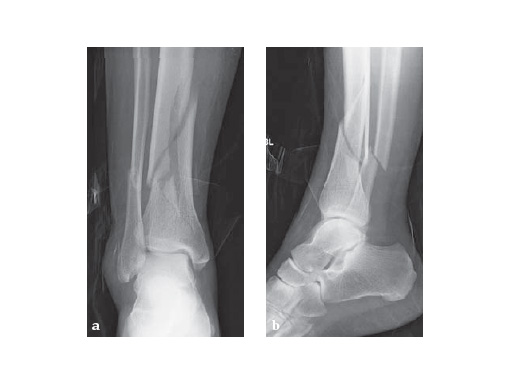

29-year-old female after a motor vehicel crash

Case provided by Sean Nork, Washington, USA

The fibula was reduced and stabilized through a posterolateral surgical approach. A small anterior incision was used to apply multiple clamps and to access the fracture reduction. A medial locked distal tibial plate was placed adjacent to the anteromedial surface of the tibia through a 4 cm distal incision. Multiple proximal screws were placed through small incisions overlying the plate.